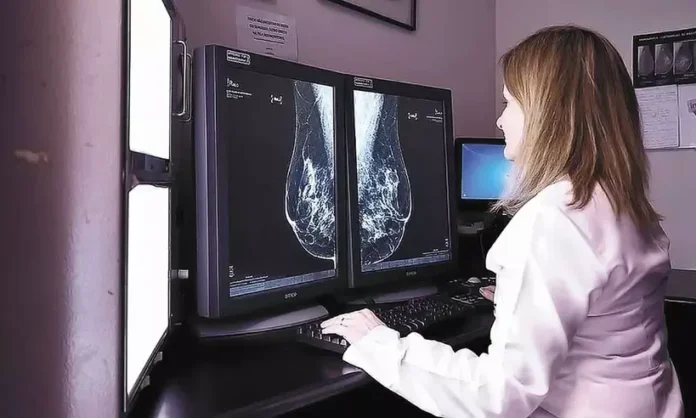

A saúde da mulher em Parintins enfrenta um momento de incerteza e preocupação devido à interrupção dos exames de mamografia no Hospital Regional Jofre Cohen. O procedimento, considerado essencial para o diagnóstico precoce do câncer de mama, está suspenso desde 2024, conforme relatos que têm chegado de usuárias que dependem exclusivamente do atendimento público.

A paralisação prolongada tem gerado angústia entre as pacientes, que se veem sem acesso a um instrumento vital na prevenção e no combate à doença. A mamografia de rastreamento é recomendada anualmente ou a cada dois anos, dependendo da idade e do histórico de risco da mulher, sendo a principal ferramenta para detectar lesões em estágio inicial, quando as chances de cura são significativamente maiores. A ausência desse serviço coloca centenas de vidas em uma situação de vulnerabilidade, reforçando a urgência na retomada imediata do atendimento.

A mamografia é mundialmente reconhecida como o padrão ouro para o rastreamento do câncer de mama. Estudos demonstram que, quando realizado em caráter preventivo e periódico, o exame é capaz de reduzir a mortalidade em até 30% nas faixas etárias de maior risco.

O câncer de mama é a neoplasia mais incidente em mulheres no Brasil, excluindo o câncer de pele não melanoma. Segundo o Instituto Nacional de Câncer (Inca), o diagnóstico em estágios avançados exige tratamentos mais longos, agressivos e de maior custo, além de reduzir drasticamente as chances de cura. O atraso de meses, ou até mais de um ano, na realização da mamografia pode fazer toda a diferença no prognóstico de uma paciente.